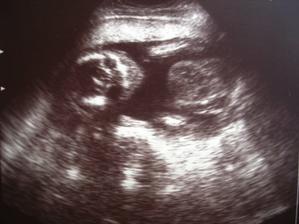

13.9. jsem dělala první testík a málem jsem přehlédla tu slabounkou čárku. Byl to menší šok, jelikož se o miminko už rok snažíme. Následující den jsem udělala další testík pro potvrzení a z nevolnosti už mi bylo více než jasné, že bude čárka silnější-a také že ano. První utz. 25.9. - 5+2tt mimi má 17mm. Druhý utz. 18.10. - 9+1tt mimi má 23,3mm. Třetí utz. 6.11. - 11+2tt. Čtvrtý utz. 29.11 - 14+4tt Malé má 16 cm. 16tt-16+3tt jsem přibrala 2 kila a začínám se pěkně cpát.Na utz. s námi byla nastávající babička. 20tt jsem zatím přibrala 4.5 kg. 21 tt další utz., váha 59kg. To s námi byl na utz. i tatínek. Začínající váha byla 53kg. 25tt kontrolní utz. 61kg. Miminko je zatím stále zadečkem dole.Tak máme 36tt, miminko už je otočené hlavičkou dole a já mám 65,5 kg. Přecházíme k doktorovi do nemocnice a čekáme kdy se prcek rozhodne přijít mezi nás, podle pana doktora to má být ještě před termínem 🙂